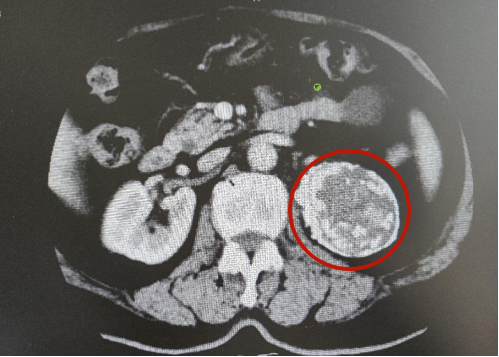

65岁的岳阿姨(化名),体检发现左肾上腺区占位病变,遂至我院泌尿外科就诊。入院后,经CT检查发现,患者左肾上腺区巨大占位性病变(病灶大小约7.1cm)。在徐医附院泌尿外科孙晓磊主任与我院泌尿外科仲委主任认真研究患者病情后,拟定手术方案,决定为岳阿姨行腹腔镜肾上腺肿瘤切除术。